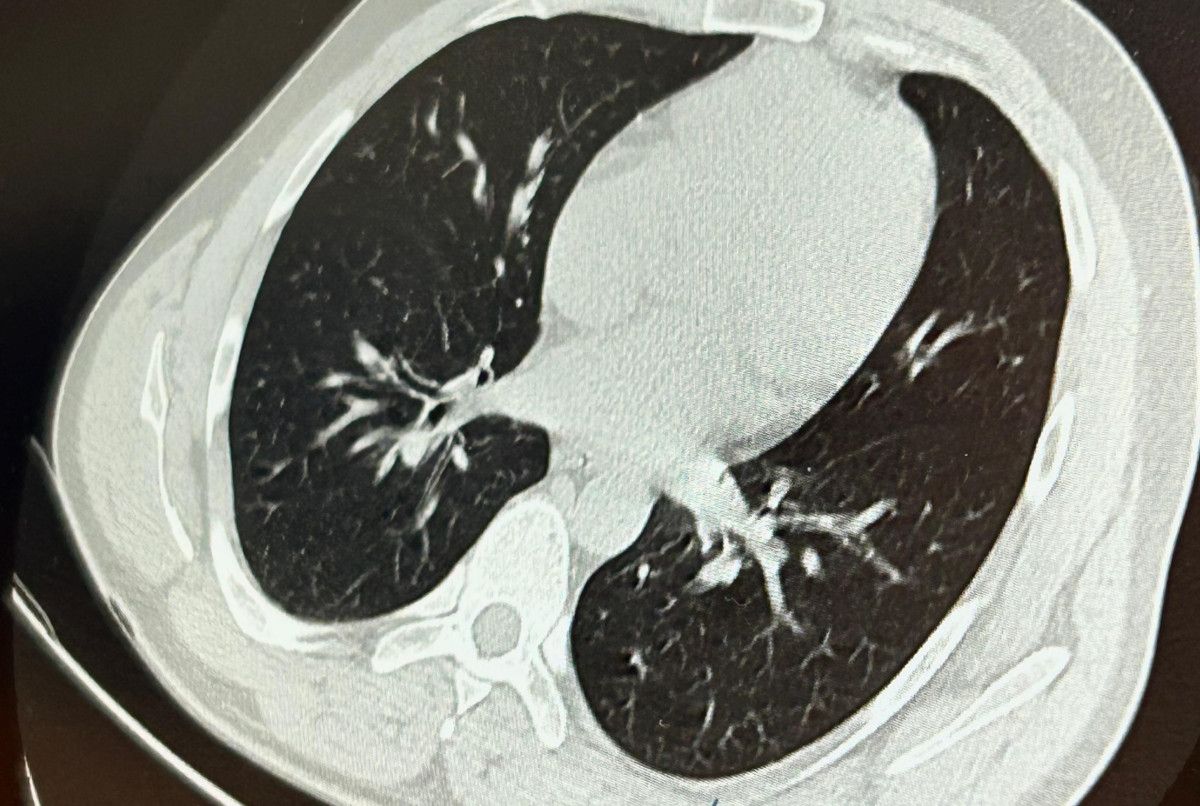

Aynı gün hastamızı hazırladık. Bronkoskopi sırasında, implant vidasının sol üst lobun anterior segment bronşuna saplanmış konumda olduğunu gördük. Üroloji kısmında taş çıkarma süreçlerinde kullanılan aygıtla müdahale ettik.

İlk olarak hastanenin ek hizmet binasında çekilen tomografi sonucunda, vidanın sol akciğerin hava yollarının yaklaşık dördüncü koluna kadar ilerlediği tespit edildiğini tabir eden Op. Dr. Aksoy, şunları kaydetti:

Sol akciğerin üst lobunda saplanmış biçimde tespit edilen vida, vidalı yapısı ve bulunduğu pozisyon nedeniyle zahmetle yerinden oynatılabildi.